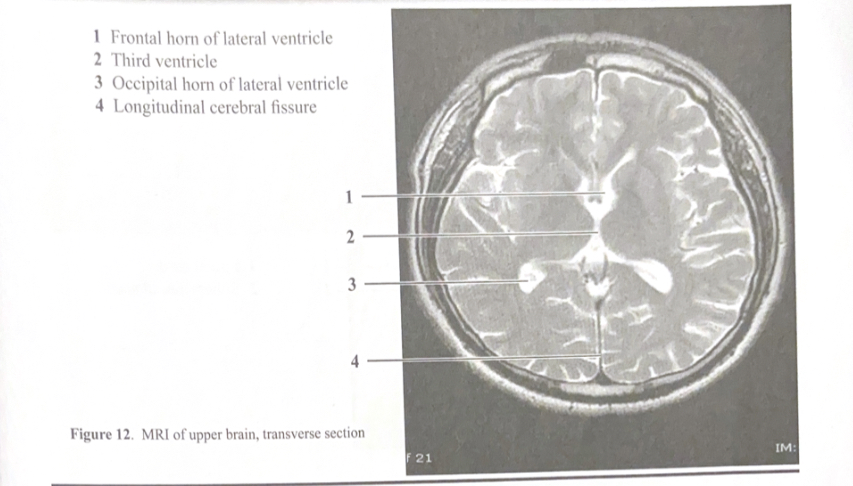

Figure 12. MRI of upper brain, transverse sectionÂ

Frontal horn of lateral ventricleÂ

Third ventricleÂ

Occipital horn of lateral ventricleÂ

Longitudinal cerebral fissureÂ